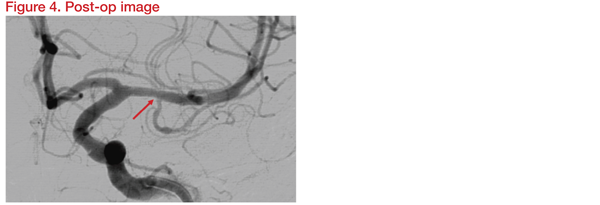

Three-Dimensional Rotational Angiography (3DRA) was carried out for assessment in detail and planning. Instruments planned for the procedure were the Gateway balloon 1.5*15mm and Wingspan stent 2.5*9mm. Following the intervention, DSA and 3DRA showed preservation of the temporal branch origin (Figure 4).

At 12 months, there was no evidence of branch thrombosis or in-stent restenosis. The patient was well and symptom free. This showed that angioplasty and stenting using Gateway and Wingspan is safe for M1 ICAD stenosis close to a temporal branch origin without delayed branch thrombosis or in-stent restenosis.